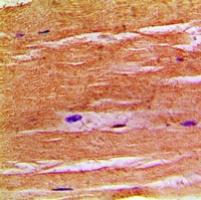

Immunohistochemical analysis of NHE8 staining in human skeletal muscle formalin fixed paraffin embedded tissue section. The section was pre-treated using heat mediated antigen retrieval with sodium citrate buffer (pH 6.0). The section was then incubated with the antibody at room temperature and detected using an HRP conjugated compact polymer system. DAB was used as the chromogen. The section was then counterstained with haematoxylin and mounted with DPX.